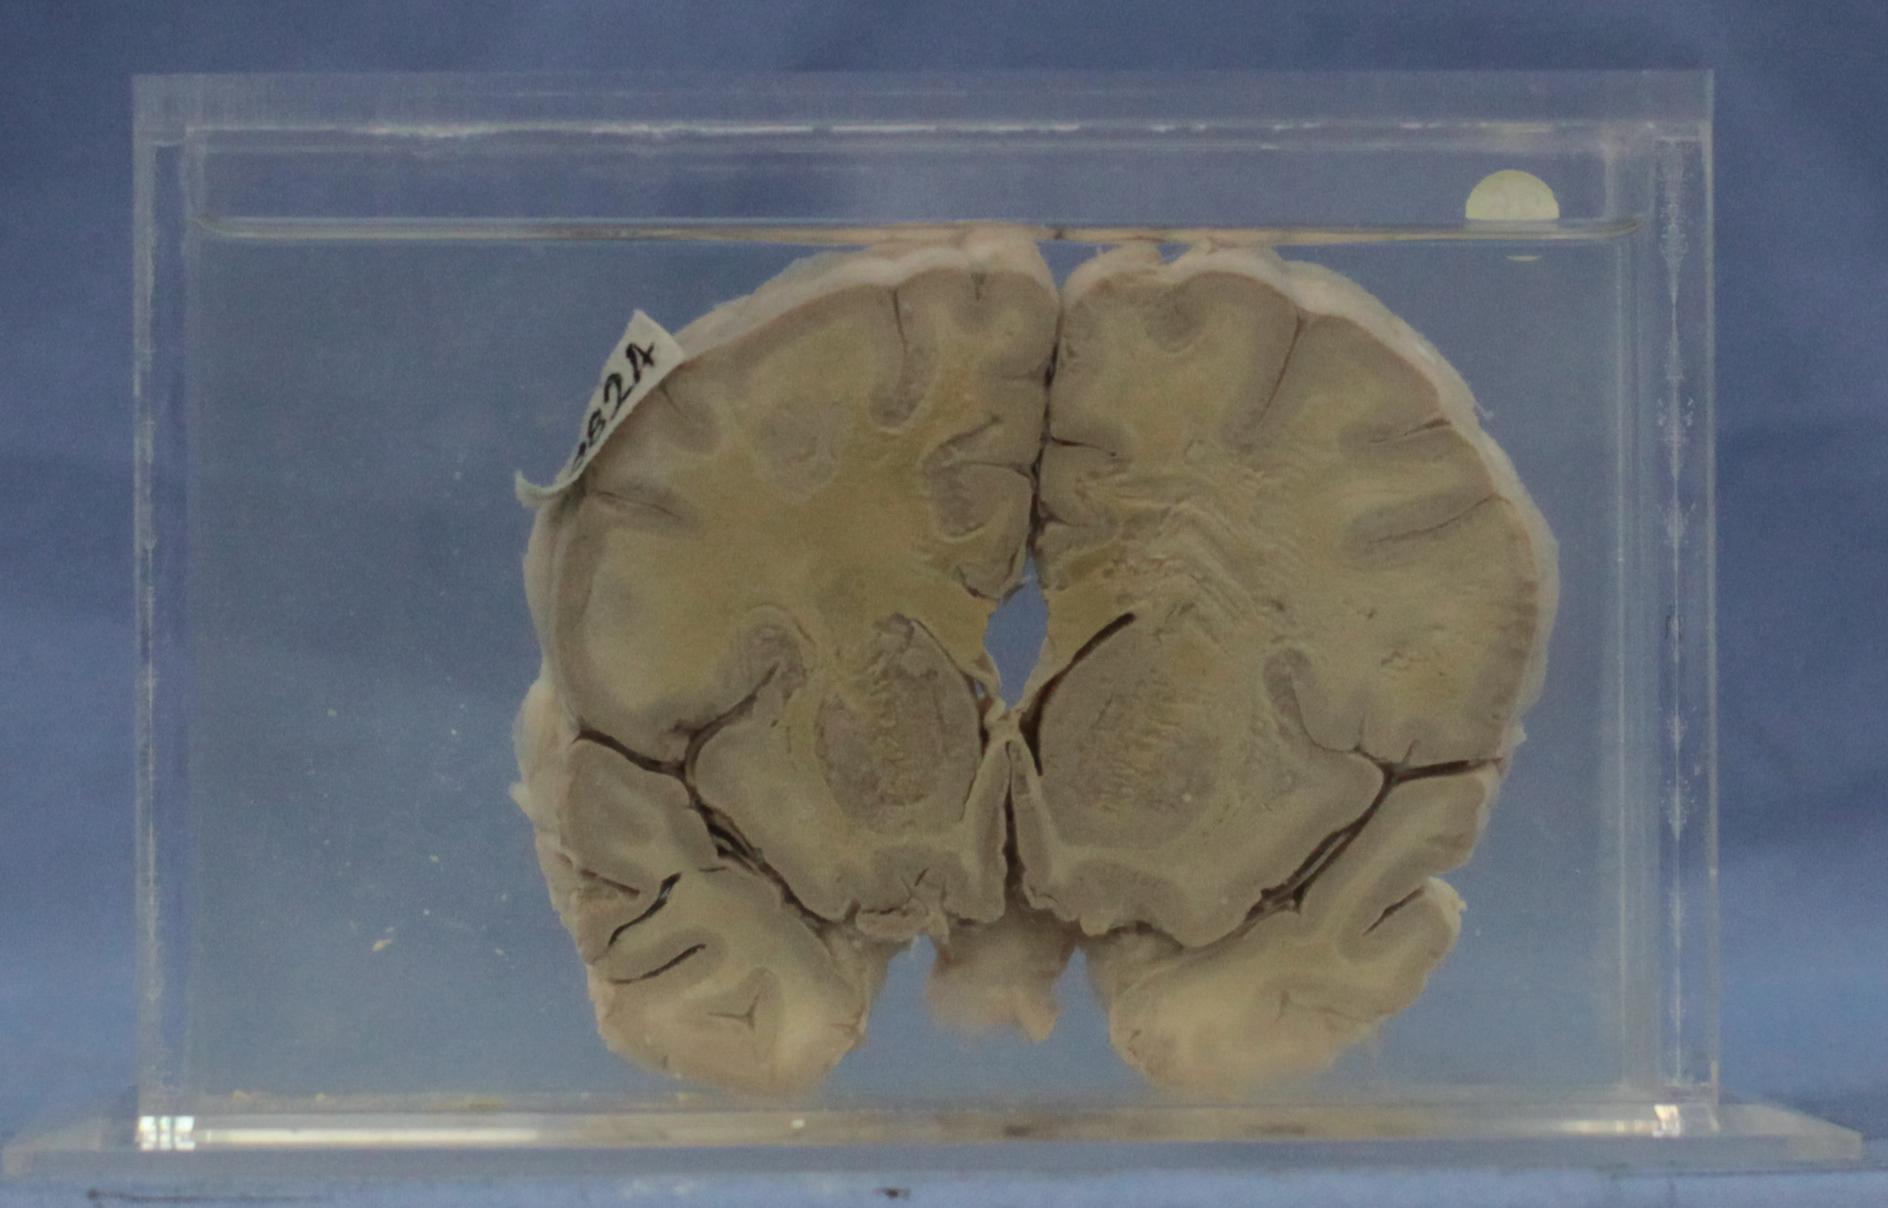

传染病87-36. 乙型脑炎

患者女性,12岁。脑的冠状切面,脑灰质(或基底核)及脑灰、白质交界处有许多白色略呈透明的点状软化灶,脑膜血管扩张充血。

脑灰质、白质内见多个筛状软化灶,其中神经元消失,有的软化灶内可见扩张的血管及组织碎片。血管周围空隙(Virchow-Robin间隙)扩大,见有淋巴细胞和单核细胞围绕(血管淋巴套),此外神经胶质细胞轻度弥漫增生,有的聚集成堆,形成胶质结节。